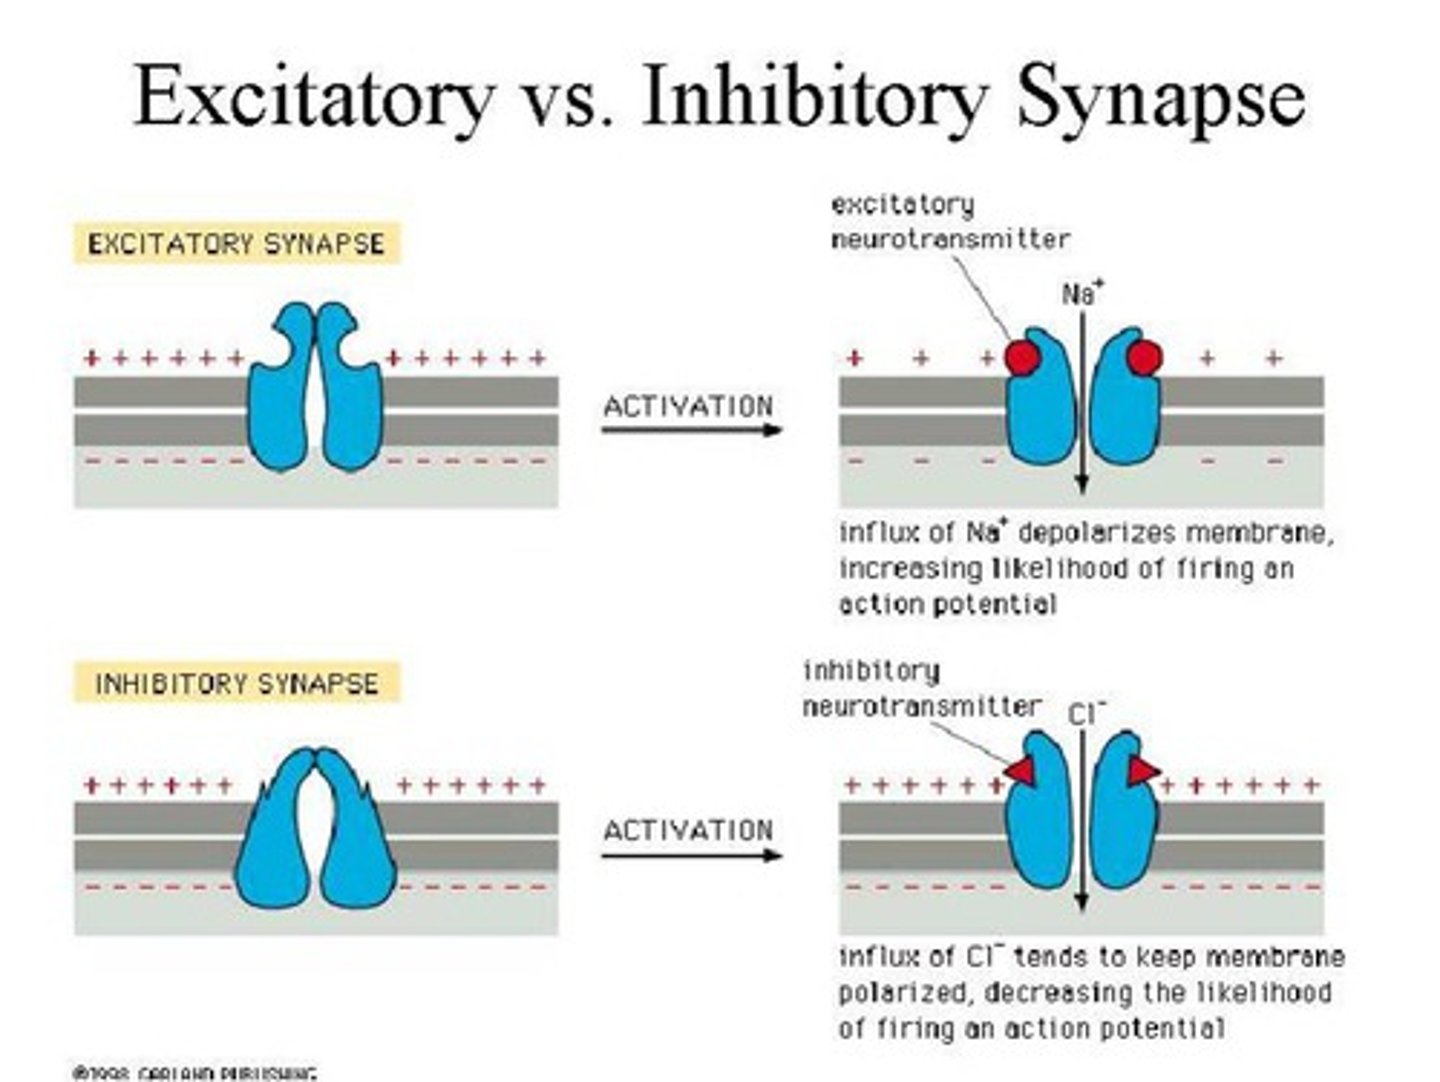

Excitatory neurotransmitter

"excites" the neuron to "fire off the message" to the next cell (includes glutamate, epinephrine and norepinephrine)

Inhibitory neurotransmitters

blocks/prevents the chemical message from being passed along (includes Gamma-aminobutyric acid (GABA), glycine, and serotonin)

Threshold

the membrane voltage that must be reached in an excitable cell (e.g., neuron or muscle cell) in order to generate an action potential

Action potential

a neural impulse (brief electrical charge) when a neuron sends information down an axon

Depolarization

a rapid rise in potential in a neuron triggered by the opening of sodium ion channels within the plasma membrane (a positive value)